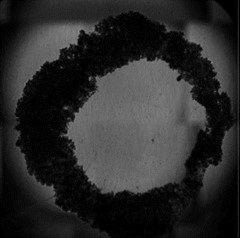

The assay we have developed is a circle with a hole in the middle, and over time, this hole is closed, much like a wound would close. When people think of a wound, they generally think of epithelial cells, fibroblasts and the other cell types that close a wound.

Fig. 1: (Left) A 96-well plate placed on the CytoSMART® Omni inside a humified incubator. (Right) 3D ring construct representing a dermal wound.